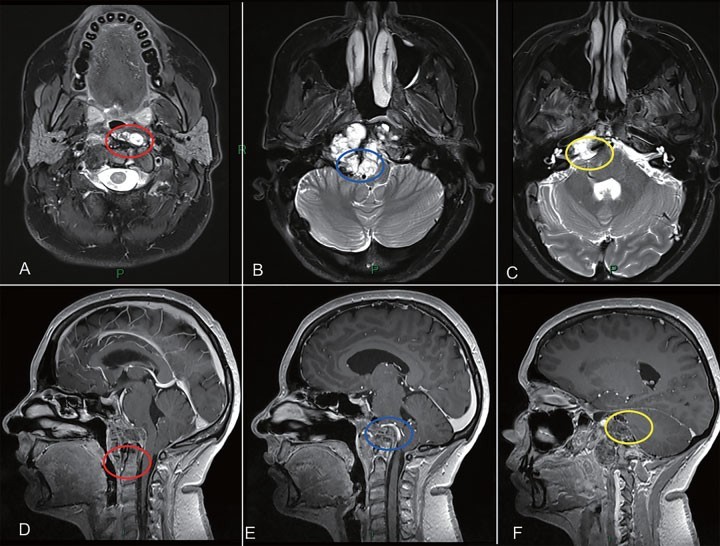

术前MRI影像图

Froelich教授提供的治疗策略:肿瘤的正中部分可以被EEA切除。另一方面,牙周区域(红色圆圈A和D),硬膜内肿瘤的扩展与后循环的接触(B和E中的蓝色圆圈),以及先前的粘连后乙状窦入路(C和F中的黄色圆圈),这些部位似乎是二颅经期的优选。(A-C) MRI T2 WI.(B-D)增强了MRI T1 WI Gd。